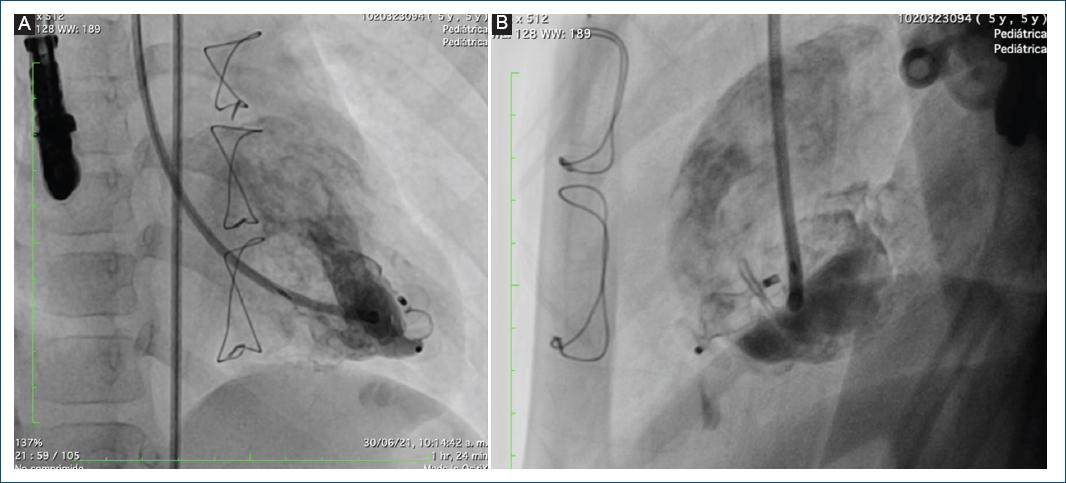

Se pasó un introductor Flexor 6 Fr hasta el ventrículo izquierdo, luego se avanzó al catéter non taper distal en el divertículo y se pasó un guía de soporte Amplatz 0.035, sobre la cual se pasó un catéter guía JR 6 Fr. Se avanzó un AVP II de 10 mm, liberando el extremo distal y el tambor central en la cavidad del divertículo y en la boca distal, y por último se liberó el disco proximal (Fig. 7). Se realizó una maniobra de Minessotta wiggle para evaluar la estabilidad del dispositivo, que permaneció estable, y finalmente se liberó (Fig. 8). La angiografía de control mostró el dispositivo en posición con oclusión del divertículo (Fig. 9).

El procedimiento se realizó con ecocardiografía transesofágica y transtorácica en forma simultánea, demostrando en la imagen final la desaparición del flujo dentro del divertículo. Se observó la bolsa pericárdica apical izquierda sin cortocircuito residual. En la punta del ventrículo izquierdo se observó una bolsa pericárdica residual ocluida completamente por el dispositivo Amplatzer Vascular Plug II de 10 mm, con función ventricular sistólica conservada y excursión sistólica del anillo tricúspide de 21 mm (Fig. 10).